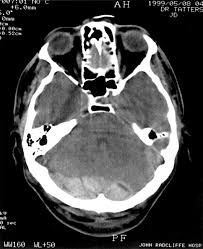

18+ Posterior Cranial Fossa Fracture Signs Pictures. The posterior cranial fossa is the most posterior aspect of the skull base housing the brainstem and cerebellum. Anteriorly it extends to the apex of the petrous temporal.

The posterior fossa contains the cerebellum, brainstem and 4th ventricle and is separated from the supratentorial compartment by the tentorium. The body of the sphenoid makes up the. It houses the cerebellum, medulla and pons.

The posterior cranial fossa is located behind the superior border of the petrous temporal bone and the dorsum sellae of the sphenoid and is the deepest of all cranial fossae. The posterior cranial fossa is the rearmost hollow or depressed area in the base of the cranium. Anteriorly it extends to the apex of the petrous temporal. The posterior cranial fossa is the most posterior and deep of the three cranial fossae.